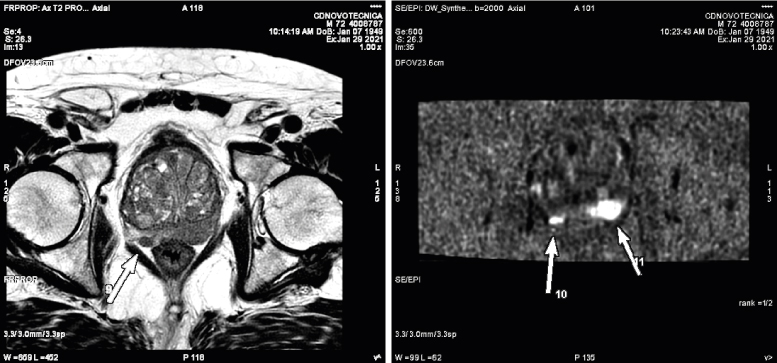

RESONANCIA MAGNÉTICA MULTIPARAMÉTRICA DE PRÓSTATA

Con este estudio podemos valorar no sólo una lesión sospechosa de malignidad en la glándula prostática, sino si existe afectación de estructuras adyacente o extensión a ganglios y hueso. Disponemos de una herramienta avanzada para realizar el informe del estudio de próstata, que facilita un mapa de la lesión, así como sus características, facilitando la localización exacta para posteriormente realizar su biopsia.

DIFUSIÓN

Clásicamente se empezó a usar la difusión en el estudio del sistema nervioso central y en la actualidad es una secuencia estándar en el estudio cerebral. Inicialmente permitía valorar la isquemia cerebral, pero en la actualidad sus usos son muy diversos, permitiendo también valorar enfermedad neoplásica, patología inflamatoria e infecciosa. En el resto del cuerpo humano básicamente se estudian lesiones tumorales y ayuda en diferenciar lesiones malignas de benignas. Está establecido ya su uso en mama, en próstata y también empieza a utilizarse en otros órganos, por ejemplo, hígado, ovario y útero. Últimamente se está usando como rastreo general en busca de tumores, especialmente metástasis, simulando un PET; es lo que se denomina RM-difusión corporal.